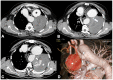

Non-traumatic thoracic aorta emergencies are associated with significant morbidity and mortality. Diseases of the intimomedial layers (aortic dissection and variants) have been grouped under the common term of acute aortic syndrome because they are life-threatening conditions clinically indistinguishable on presentation. Patients with aortic dissection may present with a wide variety of symptoms secondary to the pattern of dissection and end organ malperfusion. Other conditions may be seen in patients with acute symptoms, including ruptured and unstable thoracic aortic aneurysm, iatrogenic or infective pseudoaneurysms, aortic fistula, acute aortic thrombus/occlusive disease, and vasculitis. Imaging plays a pivotal role in the patient's management and care. In the emergency room, chest X-ray is the initial imaging test offering a screening evaluation for alternative common differential diagnoses and a preliminary assessment of the mediastinal dimensions. State-of-the-art multidetector computed tomography angiography (CTA) provides a widely available, rapid, replicable, noninvasive diagnostic imaging with sensitivity approaching 100%. It is an impressive tool in decision-making process with a deep impact on treatment including endovascular or open surgical or conservative treatment. Radiologists must be familiar with the spectrum of these entities to help triage patients appropriately and efficiently. Understanding the imaging findings and proper measurement techniques allow the radiologist to suggest the most appropriate next management step.